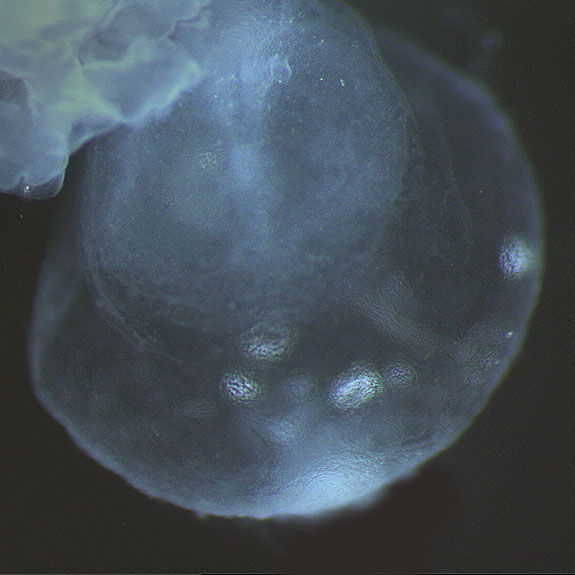

Carnegie Stage 8

Carnegie Stage 8 Definition

Age is approximately 23 postovulatory days

Length is approximately 1 - 1.5mm

External Features Include: the appearance of the primitive pit and the notochordal canal. Somites are not yet visible.